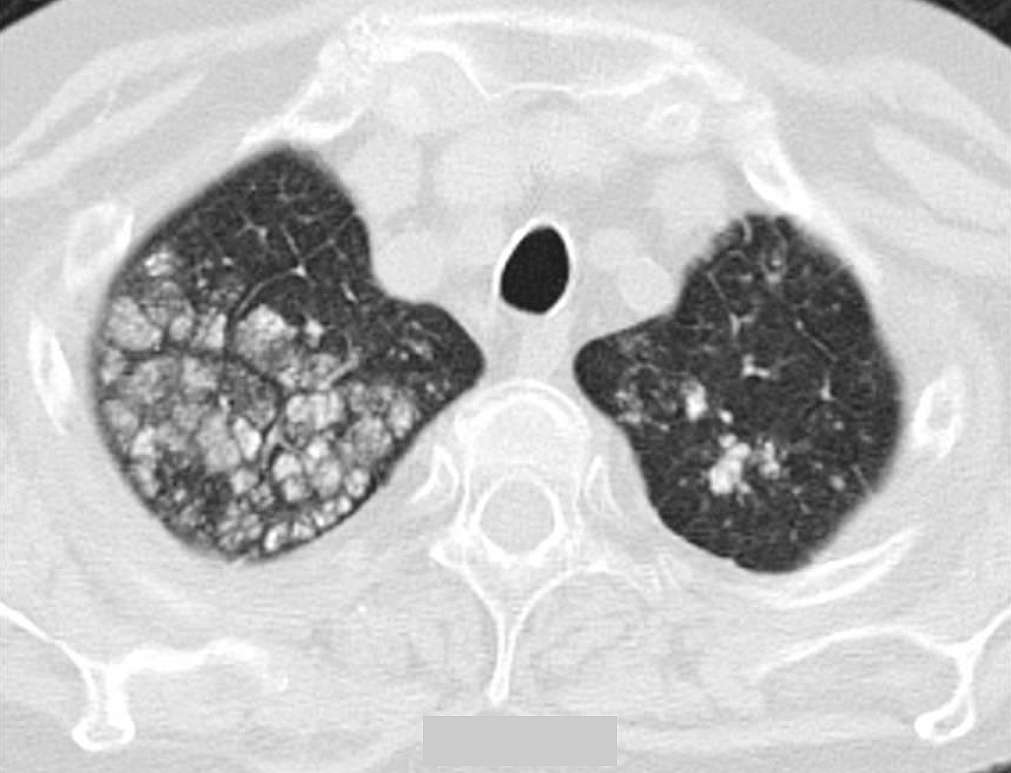

A HRCT of the chest showed multiple nodular, centrilobular and calcified opacities in the right upper lobe, but also, in lesser degree in the left upper lobe, right lower lobe and lingula (see image below). Some of the nodular opacities seen in the right upper lobe demonstrated also punctate calcifications.

On HRCT of the chest three patterns of pulmonary parenchymal calcification can be seen:

- Multiple, diffusely or patchy distributed, macroscopically or microscopically calcified nodules

- Diffusely or patchy distributed areas of ground-glass attenuation and

- Dense area(s) of consolidation